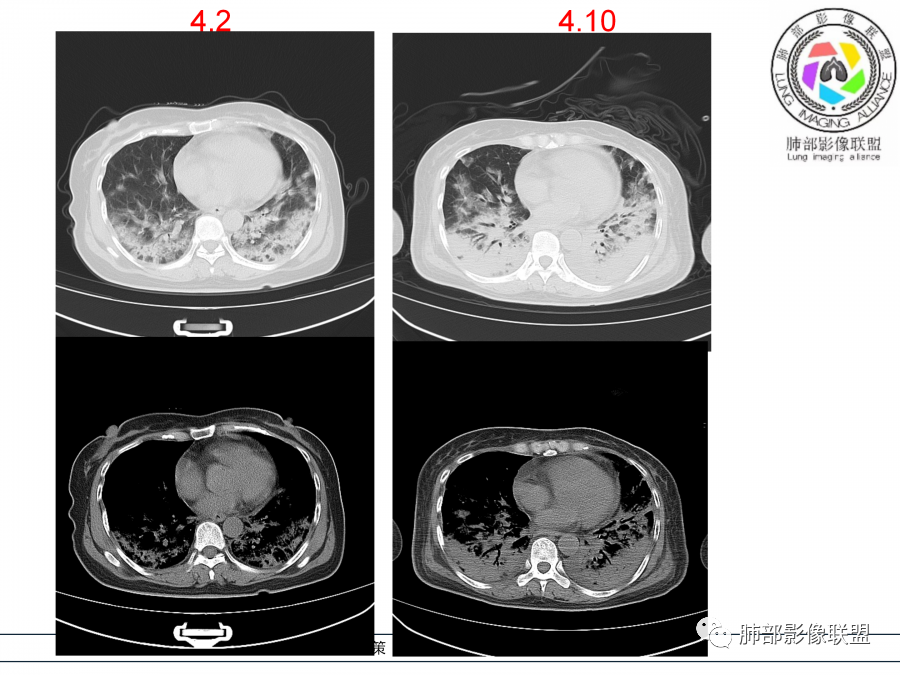

影像,第一次双肺中下叶胸膜下多发斑片状实变影,部分融合成,周围散发磨玻璃影,磨玻璃影内可见小叶间隔及小叶内间隔增厚,病变平行于胸膜,第二次间隔8天,双肺实变影明显进展,有重力作用,支气管近端堵塞,进展较快,临床有发热,血沉高,狼疮SLE阳性,考虑1:OP(机化性肺炎)2:SLE相关肺炎,建议支气管镜灌洗液病原学检测。

➢患者7天前起因受凉后出现阵发性咳嗽,无明显时间规律性,咳黄白粘痰,发热,体温最高达39.5℃,伴鼻塞、流清涕,。两肺下叶背段,后基底段为主的渗出性的病变,短时间内病变明显的增多,双侧胸腔积液,狼疮全套抗R0/SS检测阳性,考虑狼疮性肺损,机化性肺炎?鉴别结核

老年女性,咳嗽咳痰伴发热7天,白细胞不高,血沉快,降钙素原不高。其他化验未见明显异常,狼疮全套抗Ro/SSA阳性,双肺野靠近胸膜下磨玻璃实变影,支气管通畅,有充气征,沿胸膜下分布,有细网格征,7天后进展明显,实变影加重,胸膜肥厚,胸水不明显,心包少量积液?抗感染治疗无效,考虑非感染性疾病可能性大,结缔组织相关性肺病?狼疮性肺炎?机化性肺炎?鉴别病毒性肺炎。

老年女性,咳嗽咳痰发热7天。无气促。白细胞计数不高,PCT稍高,PPD(+),抗Ro/SSA阳性。CT:双肺野靠近胸膜下磨玻璃实变影,支气管通畅,有充气征,沿胸膜下分布,有细网格征。予抗生素治疗,8天后复查胸部CT见病灶范围扩大,实变影加重,胸膜肥厚,胸水不明显。抗感染治疗无效,考虑有:1.非感染性疾病:结缔组织相关性肺病,支持点:肺部CT表现为间质性炎症病变,抗RO/SSA(52)阳性;2.病毒性肺炎:患者无气促症状,可能性小;3.肺结核。

第一次双肺中下叶胸膜下多发斑片状磨玻璃及实变影,病变平行于胸膜,支气管通畅,8天后,双肺实变影明显进展范围扩大,部分支气管近端堵塞,进展较快,胸腔积液,抗感染治疗无效,考虑:非感染性疾病:结缔组织相关性肺病。鉴别机化性肺炎。

胸膜炎是SLE最常见的胸部表现,SLE急性肺损伤表现为肺出血、狼疮肺炎,虽临床罕见,但常可致死,慢性肺损伤表现为ILD。SLE弥漫性肺泡出血时,患者出现呼吸困难、发热、咳血痰,血色素下降等,HRCT表现为双肺弥漫或局灶实变影、GGO及小叶间隔增厚,此时应行支气管镜检查以确诊,急性狼疮肺炎的诊断难以界定,表现为不同程度肺功能受损,HRCT示弥漫或散在分布的气腔实变与GGO,下肺相对较重半数,患者合并胸腔积液;但目前认为,既往诊断为急性狼疮肺炎的病变很可能为急性间质性肺炎伴或不伴肺出血.仅3%的SLE患者出现ILD,以NSIP或UIP最多见,SLE相关ILD的病变常局限、程度较轻,弥漫性病变、蜂窝影很少出现,多表现为小叶间隔增厚或肺实质带,活动期的SLE患者可出现深静脉血栓,若患者出现胸痛、呼吸困难,需行胸部增强CT或CTPA以明确是否存在肺血栓、肺梗死。SLE患者胸部HRCT表现为GGO或肺实变,可能为ILD、肺出血、狼疮肺炎等,若同时出现小叶间隔增厚、不规则线影、肺结构变形意味着肺纤维化,多见于ILD等;SLE易合并感染多数为社区获得性肺炎,诊断ILD、急性狼疮肺炎、肺泡出血等需先除外感染,另外SLE患者还可出现横膈功能障碍、肺动脉高压等。